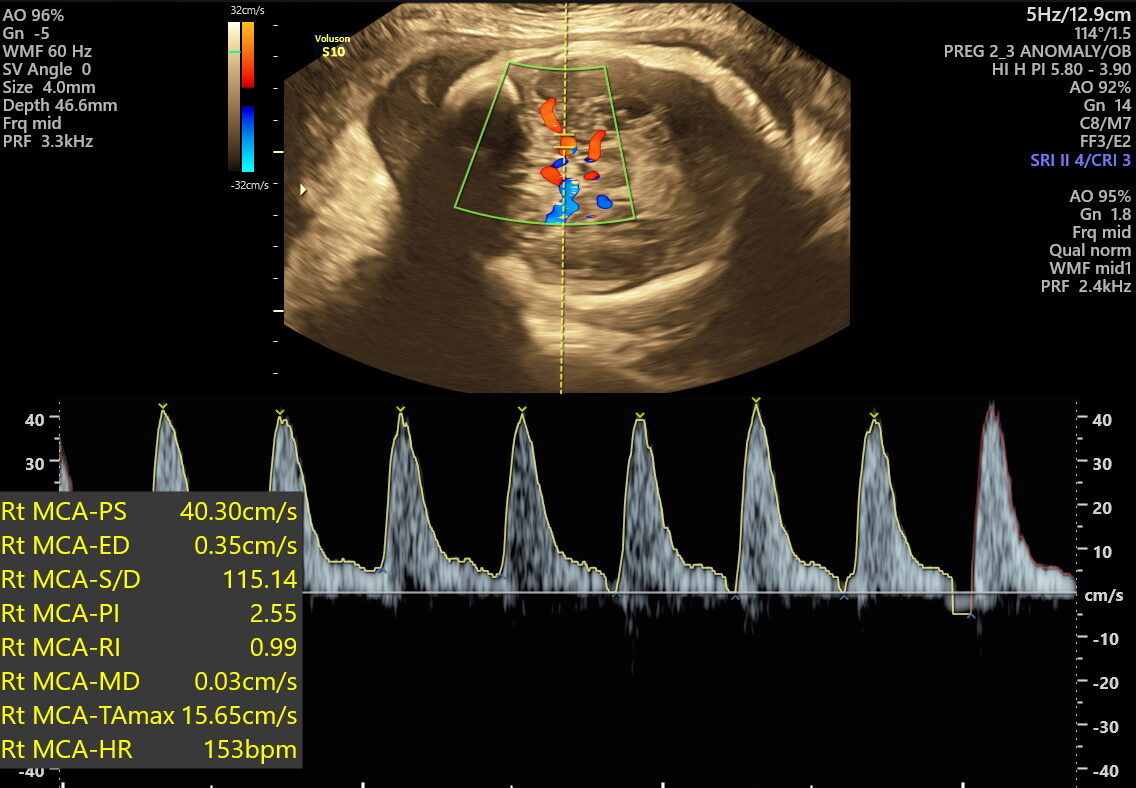

This scan focuses on confirming birth readiness and spotting sudden issues that may arise close to your due date. It includes detailed Doppler studies to check blood flow in the umbilical cord and brain, ensuring your baby gets enough oxygen and nutrients.